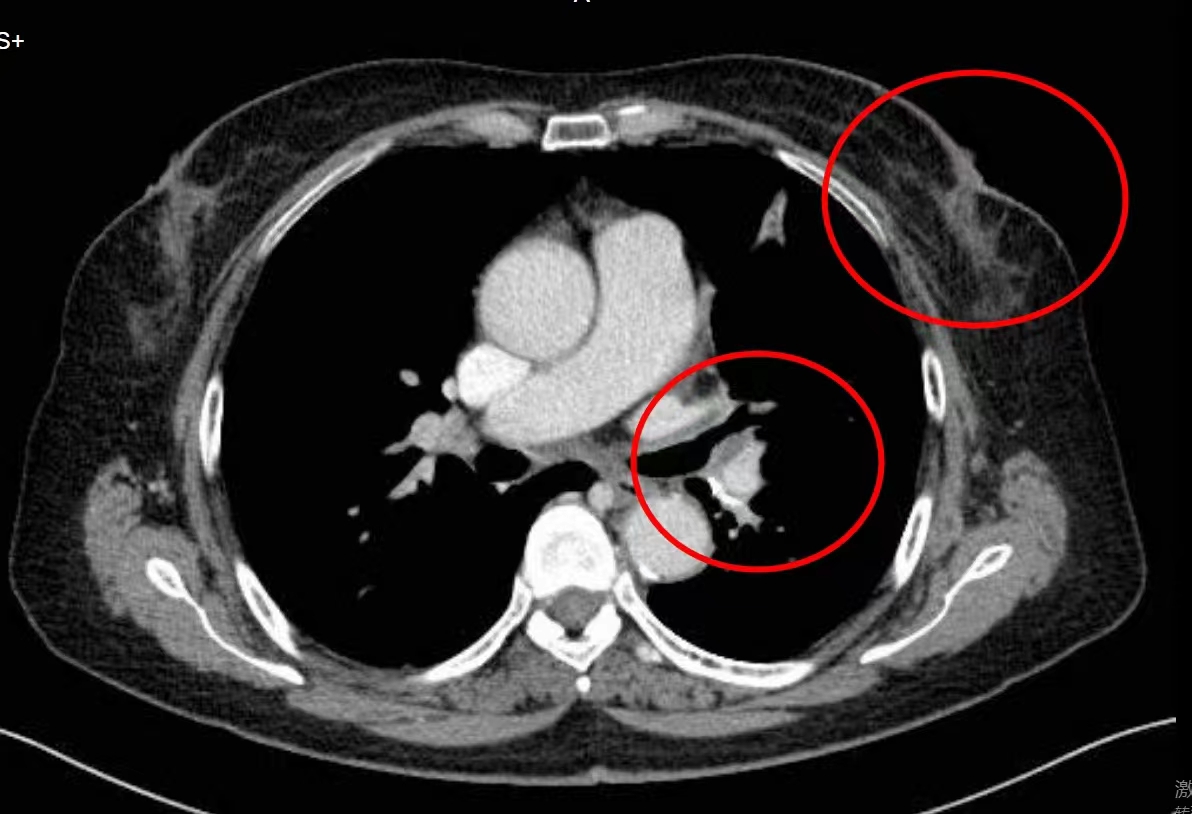

因为无意间摸到乳房肿块,并且伴有刺痛, 张女士很快到医院进行检查。在医生建议下,张女士接受了详细的检查,病理活检显示,张女士左乳腺发现了浸润癌,而且已经出现了左肺转移。

在当地医院接受了两个多月的化疗后,因为身体实在不能耐受,张女士又接受了靶向治疗。但肿瘤并没有控制住,从一开始的 3.5厘米一直增长到了4.6厘米。张女士和家属眼看化疗不耐受,靶向治疗又没能控制住病灶,赶紧寻找新的治疗方案。

在会诊时,彭主任为张女士安排了检查,发现CT示肿瘤大小已经长到了5.8公分。经多学科会诊,医生团队为张女士制定了微创+中医的综合治疗方案。医生建议,肺转移病灶行局部粒子植入治疗,乳腺原发病灶行局部动脉微创灌注栓塞术治疗。